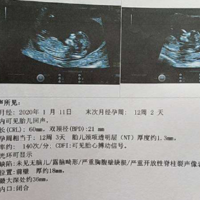

去妇幼保健院做nt检查可以在官方网站提交预约申请。NT是一种超声检查项目,NT检查又称颈后透明带扫描,是通过B超手段测量胎儿颈项部皮下无回声透明层较厚的部位。每个地区的妇幼保健院的预约方式可能有所不同,但一般来说,您可以在医院的官方网站预约,访问妇幼保健院的官方网站,查找在线预约系统或预约页面,按照相关提示填写个人信息和预约时间,提交预约申请。NT检查是孕早期产前筛查的重要项目,主要筛查可能性较高

去妇幼保健院做nt检查可以在官方网站提交预约申请。NT是一种超声检查项目,NT检查又称颈后透明带扫描,是通过B超手段测量胎儿颈项部皮下无回声透明层较厚的部位。每个地区的妇幼保健院的预约方式可能有所不同,但一般来说,您可以在医院的官方网站预约,访问妇幼保健院的官方网站,查找在线预约系统或预约页面,按照相关提示填写个人信息和预约时间,提交预约申请。NT检查是孕早期产前筛查的重要项目,主要筛查可能性较高

NT检测是孕妇产前筛查中非常重要的一个环节,可以帮助医生评估胎儿是否存在出生缺陷的风险。一般来说,医生建议孕妇在妊娠11-13周进行NT检测,如果错过这个时间窗口,会不会影响检测的准确性呢?这是很多准妈妈关心的问题。下面,我们就来详细探讨一下。什么是NT检测NT检测指的是通过超声技术测量胎儿颈部的透明带(Nuchal translucency,简称NT)的厚度,用于筛查胎儿是否存在染色体异常或其他

怀孕三月nt检查通过后女性小腹出现隐隐坠胀但不痛大多数情况下是正常表现。在检查时可能会引起宫缩、胎儿发育引起女性子宫变大等,这都是正常的;但也可能是不正常的表现,比如先兆流产,检查之后孕妇要多观察自己是否有发生不良的妊娠情况。NT检查指的是在怀孕三个月做胎儿三维彩超,注意胎儿颈后透明膜厚度,也就是NT是否正常,是一种比较重要的检查,如果发现NT则需要进行更多检查项目来确定胎儿是否存在异常。在孕3个

孕12周nt检查排除的六大畸形分别是唐氏综合征、爱德华综合征、先天性心脏病、脑脊髓管闭合不全、腹壁缺陷、其他器官畸形的风险。nt检查指的是胎儿颈项透明层,是胎儿颈后部皮下组织内液体积聚的厚度,可以通过检查胎儿颈部透明带的厚度来早期诊断婴儿染色体疾病和胎儿异常,如果出现异常情况,建议及时就医治疗。怀孕12周时进行NT(颈部透明带)检查是一项常规的产前筛查,可以帮助排除胎儿可能存在的一些先天畸形。NT

nt检查过程宝宝处于躺卧位的最佳姿势更利于检查,简单来说宝宝胎儿侧脸面对“镜头”,鼻子和脸向上,NT在画面的下方。这样的画面就是正矢位。nt主要是用于检查胎儿是否染色体异常发育,一般在产检结果上会有显示,能够帮助孕妇和医生掌握胎儿的初期发育情况。但要想检查更加顺利,宝宝的姿势也很重要,临床上也会有宝宝站着或者倒立的情况,这些姿势都不利于进行nt检查。NT检查时,医生会运用B超仪器将胎儿引导到正确的

NT值正常的范围应该在2.5mm以下,如果厚度超过2.5毫米,应当再考虑做其他的排挤检查,比如做无创dna;一般情况下,在怀孕12周胎儿双顶径应该为20mm左右,如果大于这个数值,就说明胎儿的头部左右两侧较宽,属于是异常的;怀孕12周胎儿正常的头臀长应该在5.5mm-6.5mm;胎心率应该在110-160次每分钟,如果有短暂的胎心率超过一百六十或者低于一百次每分钟也是正常现象。nt检查各项指标解读